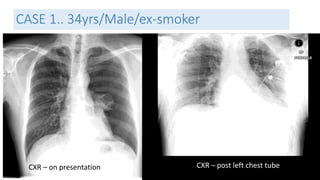

CASE 1.. 34yrs/Male/ex-smoker

CXR – post chest tube removal D4 CXR – Post chest tube reinsertion

CXR – Post op (VATS)

CT – pre op

Management and Outcome

• Diagnosis:

• Primary spontaneous pneumothorax

• Management

• Chest Tube insertion

• Gumco suction D2

• Chest tube removal on D4 and reinsertion due to recurrence ( persistant air

leak)

• VATS ( Video assisted thoracosopic surgery)

• Outcome

• Discharged well on D2 post op.

• Lung fully expanded and asymptomatic.